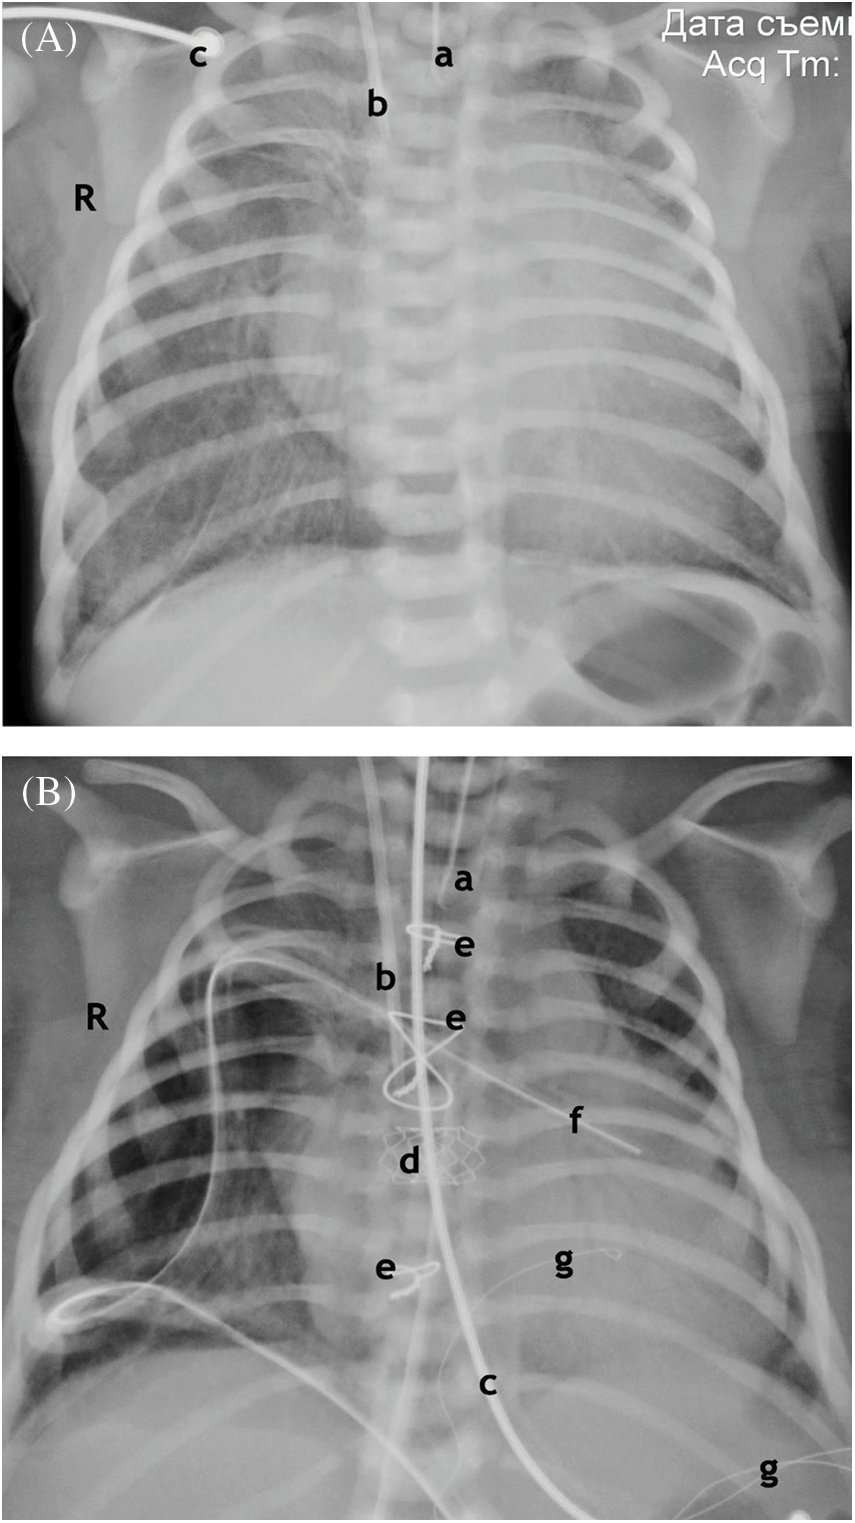

According to the X-ray of the chest: signs of acute pulmonary edema and pronounced zones of hypoventilation and atelectasis of the lungs on both sides were diagnosed (Fig. 4).

Figure 4: Chest X-ray. (A) Anterior projection. Before the operation. 1 h after birth. Enlargement of the shadow of the heart. Signs of pulmonary edema. Atelectasis of the upper lobe on the right, hypopneumatization on both sides. (B) Anterior projection. After operation. Age 7 days. Resolution of pulmonary edema. Atelectasis of the upper lobe on the right, Improvement of pneumatization. Shrinkage of the shadow of the heart

Notes: End of the endotracheal tube (a). End of the central venous catheter (b). ECG electrode (c). Stent at the atrial septum level (d). Wire ligatures of the sternum (e). The drainage of the right pleural cavity, pericardium (f). Temporary pacing electrodes (g).